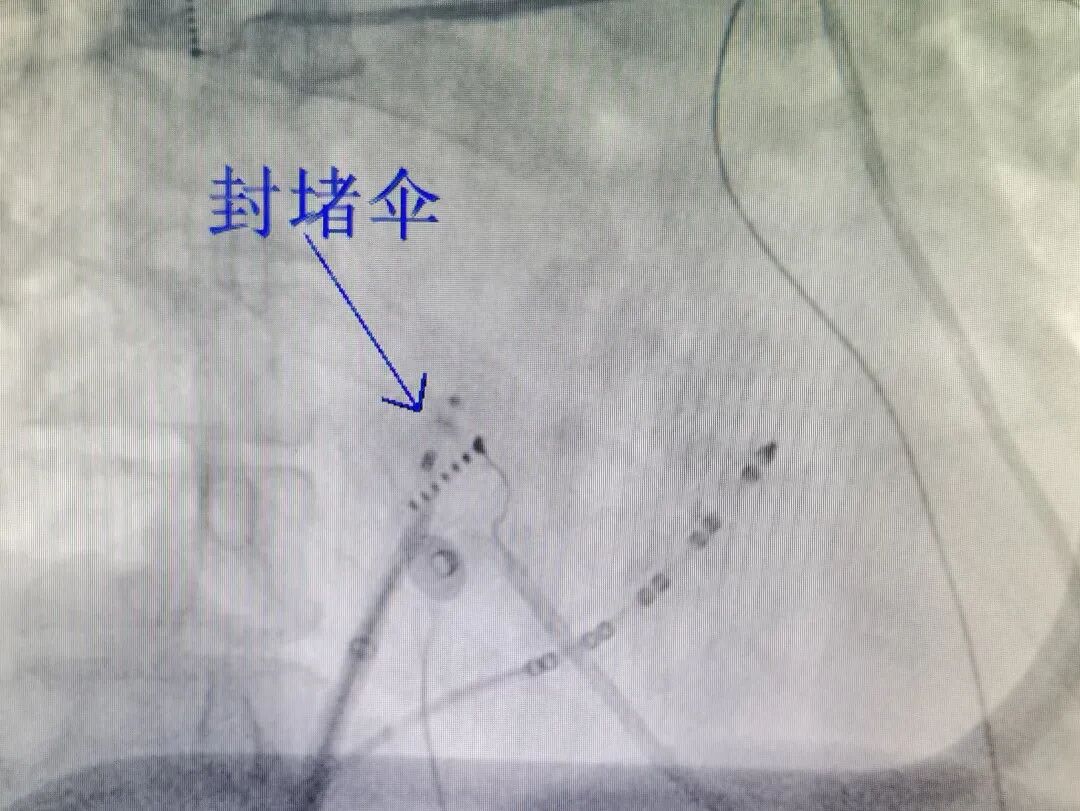

对于房颤患者而言,射频消融术是常规且有效的治疗手段,该手术通常需要穿刺房间隔,将导管送至左心房进行操作。然而,赵阿姨曾进行过PFO封堵术,封堵伞占据了卵圆窝的大部分空间,留给房间隔穿刺的空间极为有限,导致房间隔穿刺困难,且后续消融导管操作难度也随之增加。

术前,团队对赵阿姨的CT影像进行了反复细致的讨论,不放过任何一个细节,最终确定了卵圆窝封堵伞右房面边缘剩余的可穿刺部位,为手术的开展奠定了坚实基础。

在中山医院专家的悉心指导下,吴淞中心医院心血管内科主任施鸿毓与主治医师张振洲密切配合、精准定位,在封堵伞后下缘外侧成功完成了房间隔穿刺。

术中精准定位后成功进行房间隔穿刺